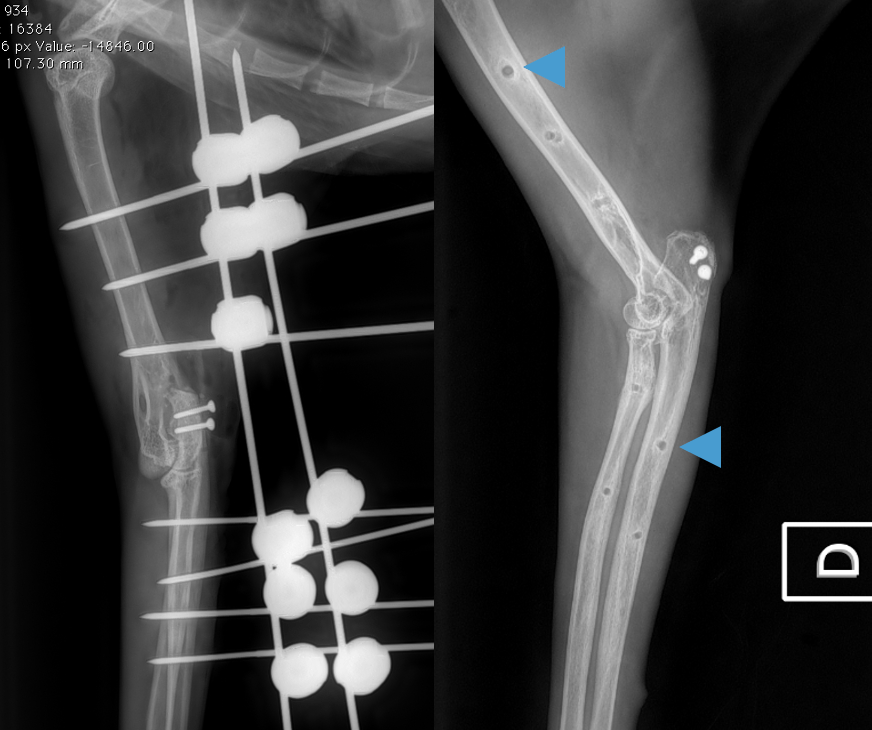

L’avulsion du triceps chez un chat

Radiographie du coude D d’un jeune chat de 11 mois présenté pour boiterie aigue avec supression d’appui : quel est votre diagnostic ? ☑️ Une fracture du…